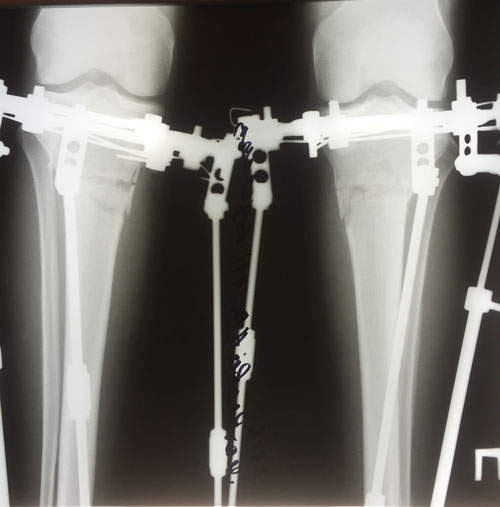

Рентген в 20 дней после операции.

Ортопедическая ось идеальная, искусство хирурга на 5+

Зафиксировать аппараты и домой!